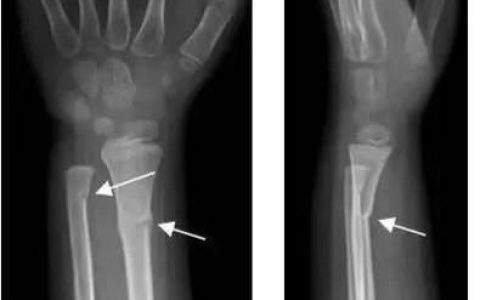

桡骨远端骨折四十天手背还肿

按照您的描述拆除了外固定,应该是采取了手法复位+石膏外固定保守治疗,因为采取了内固定手术的话一般不需要外固定。由于桡骨远端位于我们的腕关节部位,拆去外固定以后仍然觉得肿,多见于两种…